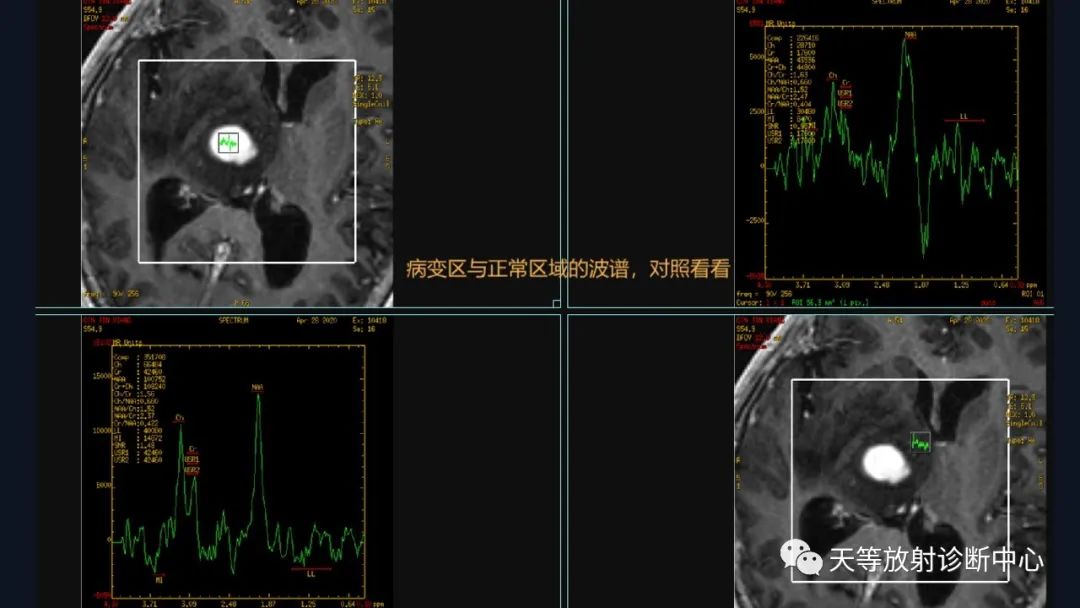

看到最高的波,就是正常NAA

NAA的波谱位于2.0 ppm处,其在脑内几乎全部位于神经元内,是公认的反应神经元功能的内标物,它的浓度多少可反映神经元的功能状况。

第二个高峰就是Cho,胆碱峰Cho的波谱位于3.2 ppm处,包括胆碱、磷酸甘油胆碱、磷酸胆碱和磷脂酰胆碱,反映脑内总的胆碱量,这些物质主要存在于细胞膜上,是细胞膜磷酯代谢的一个组成成分参与构成细胞膜并反映膜的更新,其浓度的改变反映细胞膜合成和降解的变化

第三个峰Cr的波谱位于3.02 ppm处,包括肌酸与磷酸肌酸,其作为高能磷酸化的储备以及ATP和ADP的缓冲剂可能对维持脑细胞中的能量依赖系统发挥作用。由于Cr在同一个体脑内不同代谢条件下均保持相对稳定,故Cr常作为波谱研究的内参照。以Cr为参照的NAA/Cr和Cho/Cr比值在一定程度上反映了NAA和Cho浓度的变化。

第四个峰LL:波峰在0.9~1.3ppm。出现脂质波强烈提示组织凝固性坏死,肿瘤和炎症均可表现脂质波增高。正常LL峰不高。

第五个峰:MI 波(肌醇):波峰在3.56ppm。肌醇为激素敏感性神经受体的产物,也是磷脂酰肌醇和二磷酸磷脂酰肌醇的前体物。MI/Cr比值可以提供肿瘤分级信息,良性肿瘤该比值高于恶性脑肿瘤。也可用于脑肿瘤鉴别诊断,该比值明显增高提示非肿瘤性病变。

异常的波谱情况

NAA的波谱位于2.0 ppm处,其峰值降低,说明神经元细胞受破坏

第二个高峰就是Cho,胆碱峰Cho的波谱位于3.2 ppm处,峰值下降,细胞膜合成和降解受破坏

第三个峰Cr的波谱位于3.02 ppm处,包括肌酸与磷酸肌酸,峰值改变不大,比较恒定。

第四个峰:LL峰倒置,增高

第五峰:MI增高

文献报道:Lip峰的出现提示淋巴瘤

可以鉴别胶质母细胞瘤或转移瘤